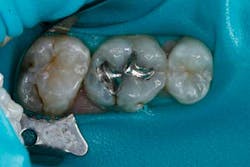

An example of an ideal case for which bulk filled composite (i.e., Tetric EvoCeram® Bulk Fill) is indicated is a 43-year-old female who presented with a defective amalgam restoration on the occlusal of tooth No. 14 (Figs. 1 and 2). The treatment plan involved removing the defective amalgam restoration, any secondary caries, and restoring the tooth with a direct bulk-fill composite (i.e., Tetric EvoCeram® Bulk Fill).

The tooth was prepared and a total etch technique utilizing 37% phosphoric acid was performed (Figs. 3 through 5). After the etchant was rinsed, a desensitizer was placed and blotted to leave a moist dentin surface for bonding (Fig. 6). The bonding agent was applied; the ethanol solvent was air evaporated using a warm air dryer; and the adhesive light-cured for 10 seconds (Figs. 7 and 8).